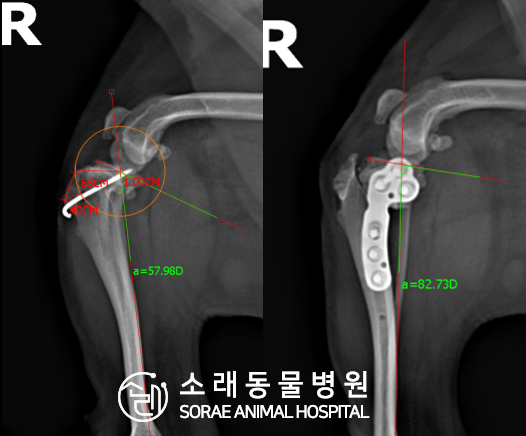

계산식으로 사전에 계획해두었던 플랜에 따라 경골을 절제하고

플레이트와 스크류를 사용하여 임플란트를 적용해 주었습니다.

반대 방향으로 밀려나 어긋나있던 대퇴골과 정강이가

제 자리를 찾으면서 무릎의 각도가 교정된 것을 확인할 수 있습니다